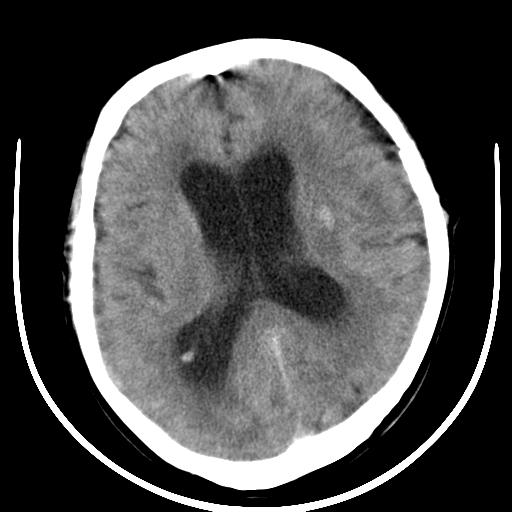

标题: CT16838:男58岁,意识不清2小时,请会诊出血部位该如何写。 [打印本页]

标题: CT16838:男58岁,意识不清2小时,请会诊出血部位该如何写。

呵呵  这样的做ct效果也太差了吧1首先 看见脑室扩大 1、左侧壳核出血。不足以解释临床的昏迷。

1)脑干、左侧桥小脑臂及小脑蚓部出血破入蛛网膜下腔。2)左侧基底节区灶性出血,不排除钙化灶。3)脑室系统少量积血。4)脑积水。

(患者病情危重,出现不自主运动——是引起图像质量不佳的主要原因)